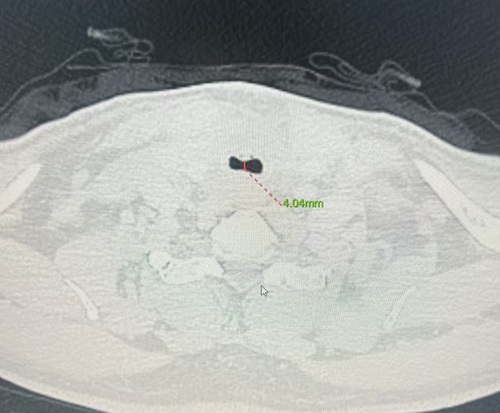

图1术中狭窄的气管;图2术前气管影像;图3术后气管影像

患者薛伯伯罹患甲状腺乳头状癌,肿瘤不仅侵犯被膜及周围结缔组织,更严重压迫气管,导致气管变形。CT提示气管受压显著,随时可能发生气管塌陷或术中大出血,引发窒息风险。此类病情常涉及气管切除重建、神经保护、术后气管插管及ICU监护等多重挑战。